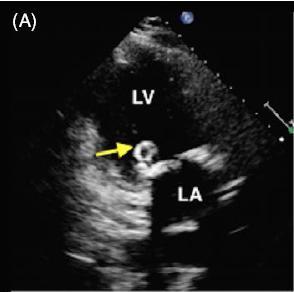

患者女,42 岁,以「急性视网膜动脉闭塞」病史就诊,既往无慢性疾病。经胸超声心动图检查发现二尖瓣后叶可见一囊状结构,可活动(图 A 和 B)。二维和实时三维经食管超声心动图检查显示一柔软的圆形结构附着于二尖瓣后叶,活动性良好(图 C ~ G)。主动脉弓、左心房、左心耳和左心室均正常。根据病变形态特征及超声表现,诊断为二尖瓣附瓣。其它影像学检查如 MRI、颈动脉多普勒超声均无异常。基于上述检查结果,考虑急性视网膜动脉闭塞为 AMVT 所致,建议外科手术切除二尖瓣附属组织,但是患者拒绝,选择随访观察。

图 A 经胸超声心动图显示二尖瓣后叶可见一囊状结构,可活动